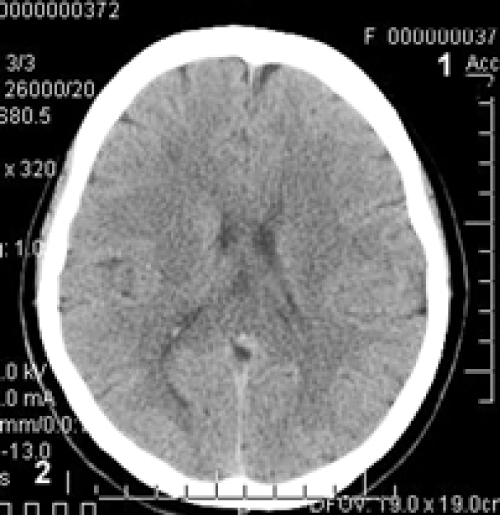

Figure 1: Patient H.: Female, 60 years old: CT of the brain. Before the Intervention: 1) moderate expansion of the subarachnoid space; 2) moderate heterogeneous post-ischemic cyst in the right middle cerebral artery region.